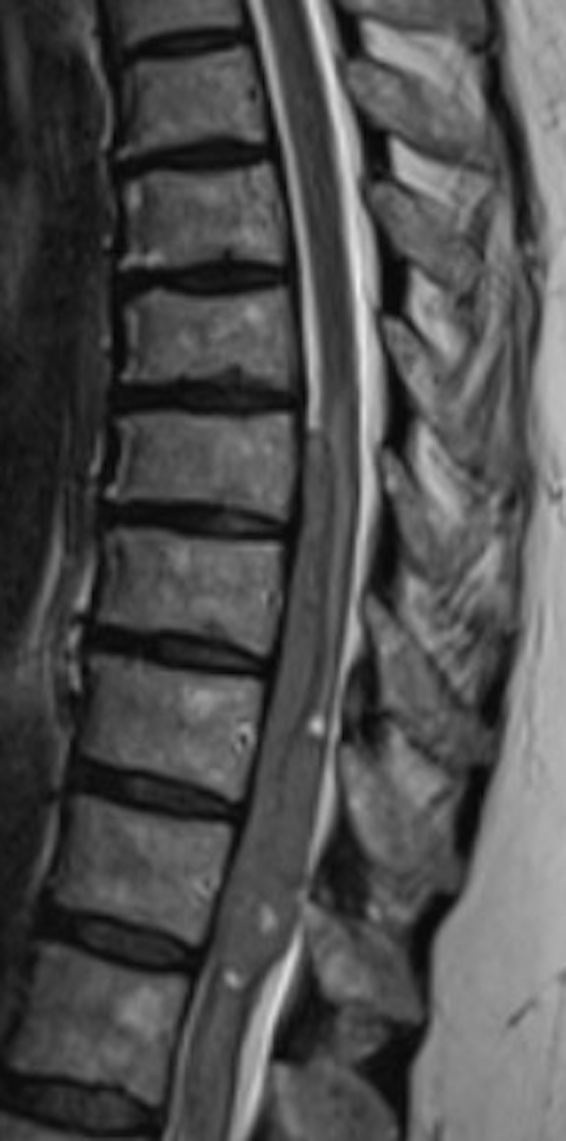

61-year-old woman with worsening low back pain and weakness

A 61-year-old woman was evaluated for gradually worsening low back pain. The pain progressed to left leg pain that radiated to her left foot, with perceived weakness.